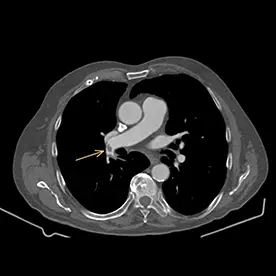

Als Zufallsbefund zeigte sich in der Kontrastmittel-gestützten CT- Untersuchung des Thorax eine bilaterale Lungenarterienembolie mit Kontrastmittelaussparungen in der proximalen Arteria pulmonalis beidseits sowie auf Segment- und Subsegmentniveau (Bild 7-1 und 7-2, Pfeile). Nebenbefundlich zeigt sich eine kalzifizierende Arteriosklerose.

Bild einer bilateralen subakuten Lungenarterien-Embolie (LAE).